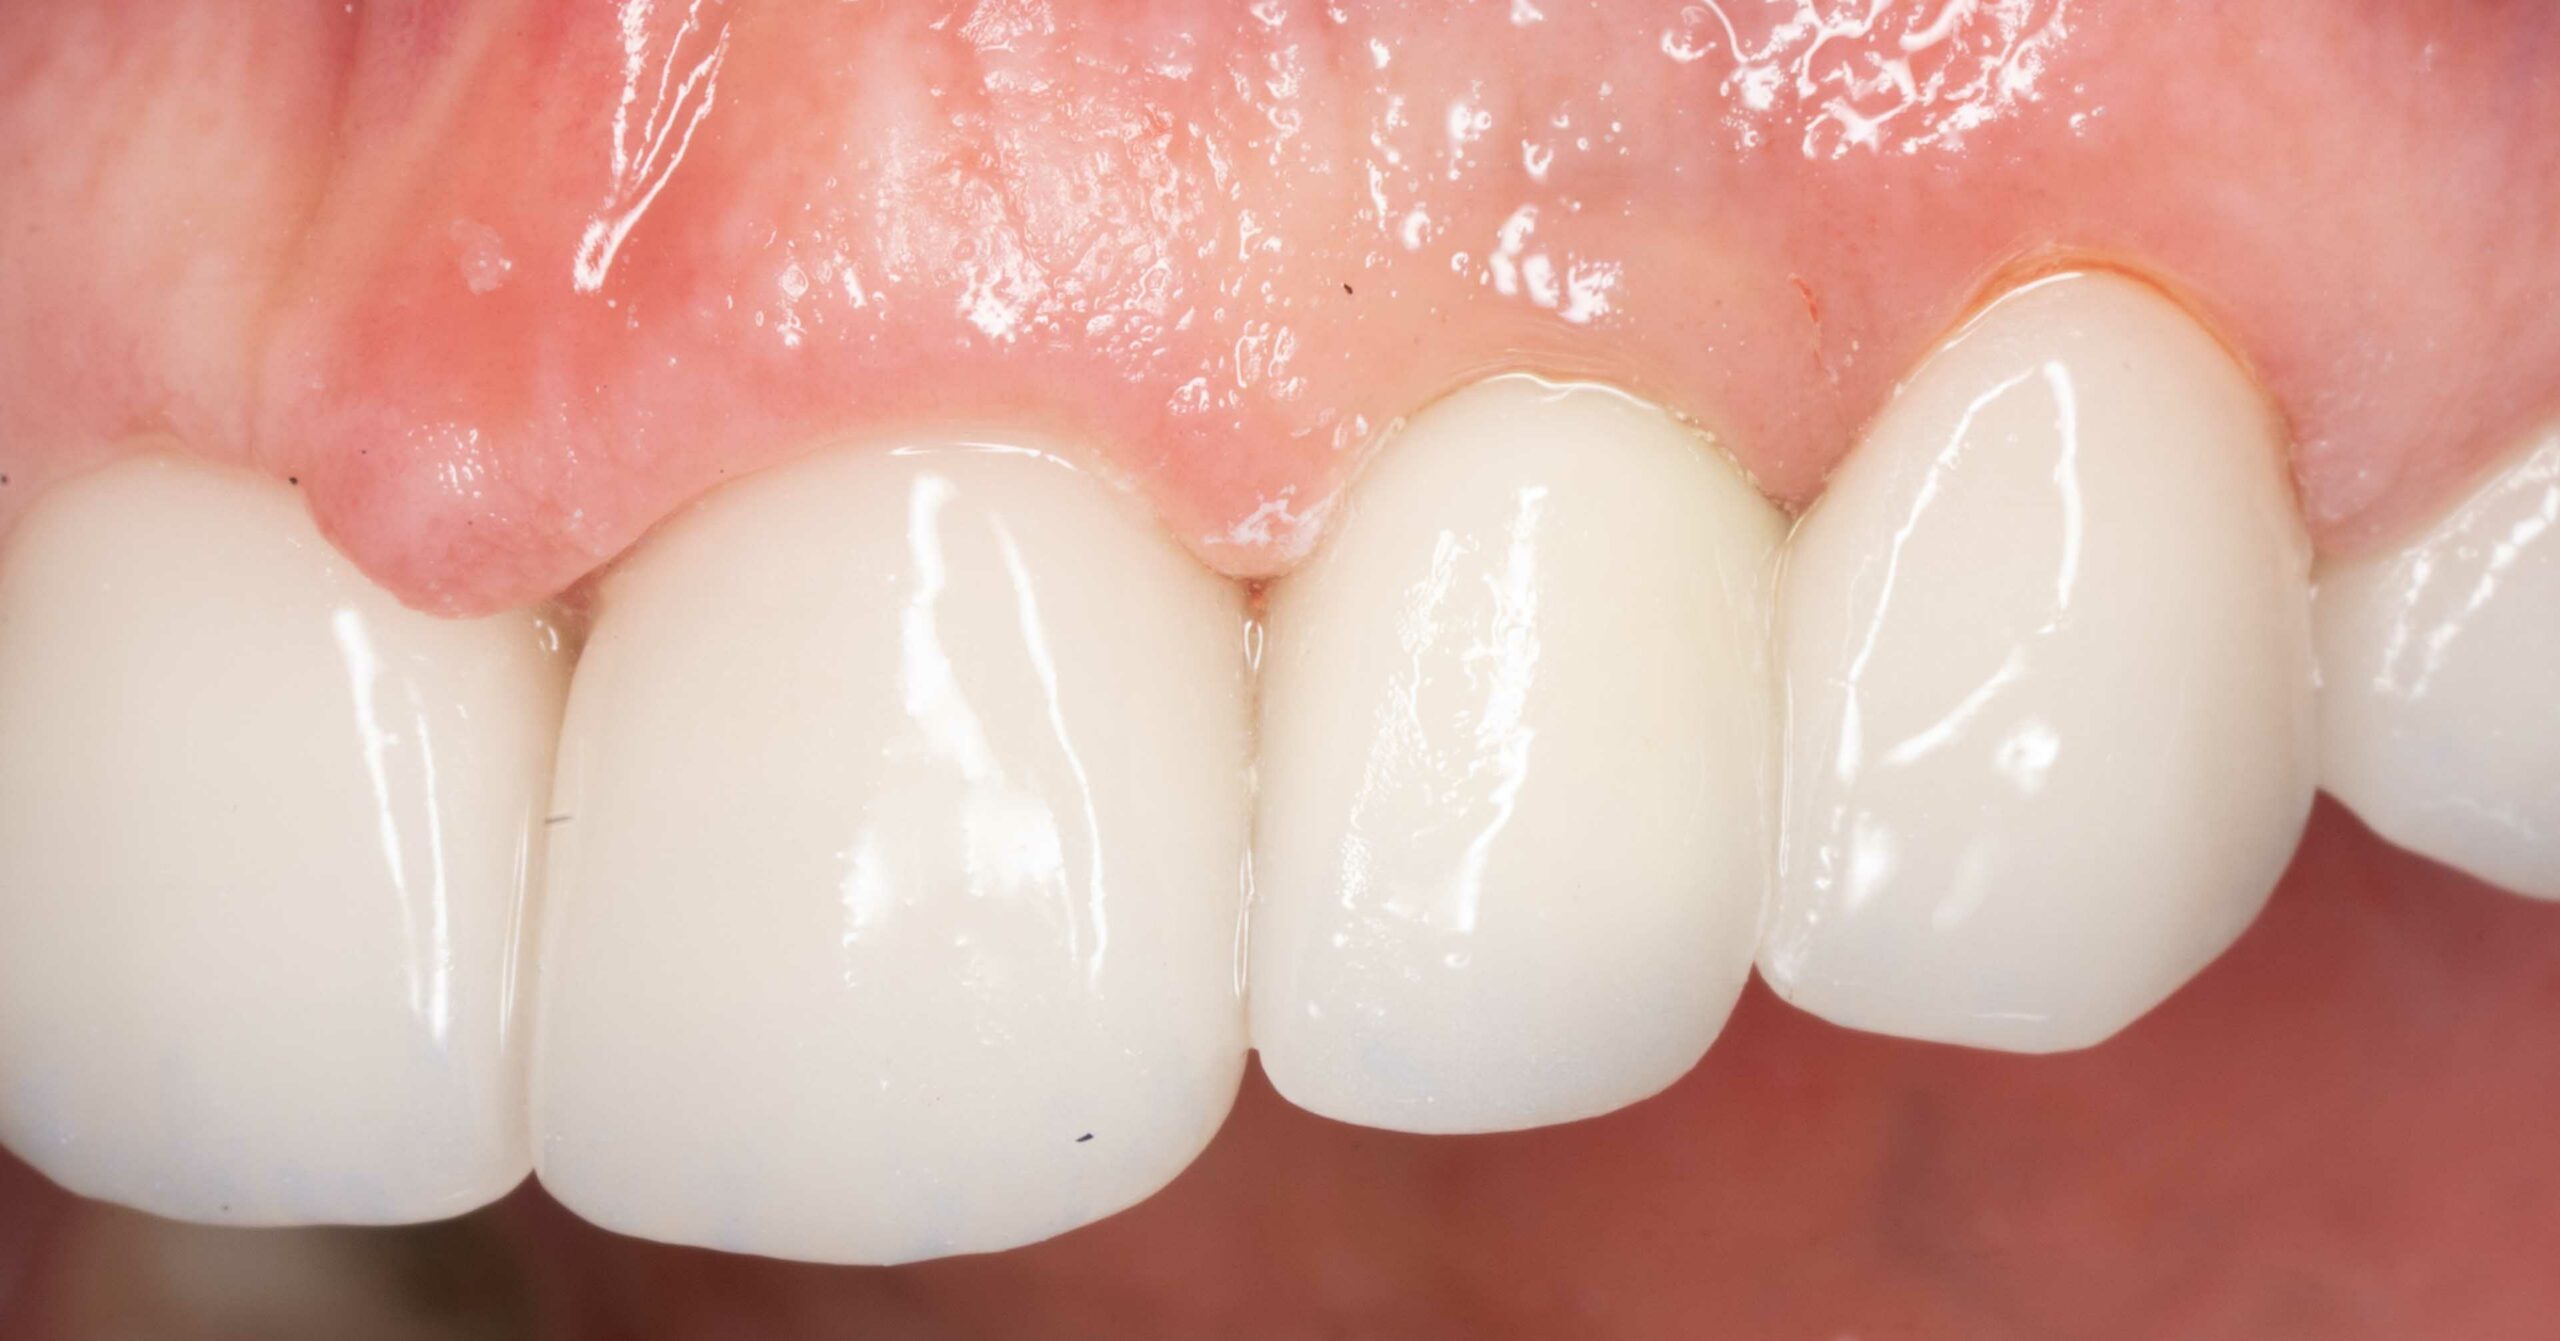

utrata zęba po urazie

Nasi pacjenci mogą liczyć na niezwłoczną oraz profesjonalna pomoc w każdej, nawet najbardziej stresującej sytuacji. Młoda pacjentka zgłosiła się z powodu utraty zębów przednich, do czego doszło kilka dni wcześnej, w wyniku potracenia przez kierowce elektrycznej hulajnogi. Leczenie polegato na niezwtocznym wprowadzeniu implantów zebowych oraz tymczasowej odbudowie zebów, dzieki czemu pacjentka jeszcze tego samego dnia odzyskata peten usmiech. Wprowadzenie implantów w odcinku przednim stanowi niezwykte wyzwanie. Aby osiagnac naturalny wyglad oraz wysoka estetyke czesto wymaga dodatkowych zabiegów regeneracyjnych na okolicznych tkankach miekkich oraz twardych. Przedstawiony efekt to uśmiech po wykonaniu ostatecznej odbudowy protetycznej.